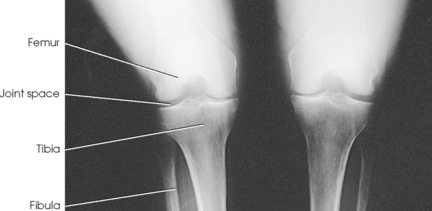

Leach et al.1 recommended that a bilateral weight-bearing AP projection be routinely included in radiographic examination of arthritic knees. They found that a weight-bearing study often reveals narrowing of a joint space that appears normal on a non–weight-bearing study.

• Adjust the patient’s position to center the knees to the IR.

• Place the toes straight ahead, with the feet separated enough for good balance.

• Ask the patient to stand straight with knees fully extended and weight equally distributed on the feet.

• Center the IR ½ inch (1.3 cm) below the apices of the patellae (Fig. 6-127).

Structures shown: The resulting image shows the joint spaces of the knees. Varus and valgus deformities can also be evaluated with this procedure (Fig. 6-128).